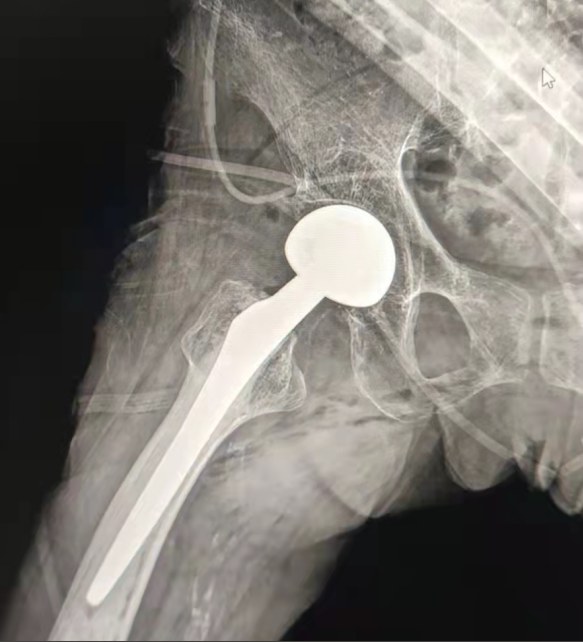

Partage de cas | Un patient de 70 ans, a reçu le remplacement total de la hanche avec le système de hanche cimenté par Lepu

Système cimenté de hanche:

Matériaux d'alliage de Co-Cr-Mo

Haute résistance à l'usure

Grande résistance mécanique

Conception de fil d'épaule

Facilement installer, tenir et ajuster l'angle

Traitement de surface poli

Pour obtenir une excellente croissance osseAssurer la stabilité de la fixation précoce

12/14 Conception standard de chandelle

Proximal Mix Anatomy

Design Collection Europe et USA Caractéristiques de la tige

Traitement distal de coupe d'Adge des deux côtés

Réduire la pression dans la cavité médullaire